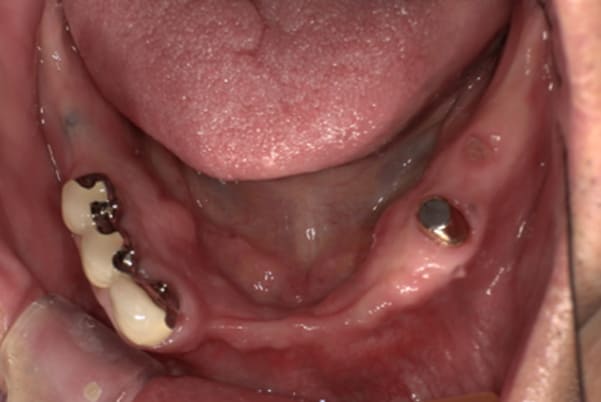

症例レポート[CASE.04]

前歯がとれて痛い、

食事もできず、見た目も悪い

- 女性(60代)

- 前歯がとれて、痛い、食事ができない、見た目が悪く人に会えないので何とかしてほしい

- 上顎精密金属総入れ歯

- 下顎精密金属部分入れ歯

- 磁性アタッチメント(白金加金) 1歯

上前歯はブリッジの差し歯により根が折れ炎症を起こしお痛みのある状態でした。

原因は長期使用により下の義歯の歯が削れたことにより、下前歯が上前歯を突き上げ強い力が加わっていたことが根本的な原因と考えられます。

治療前は、奥歯が下がり、かみ合わせが乱れています。適切な入れ歯はそのままのかみ合わせで義歯を作るのではなく治療後のように、前歯から奥歯までのラインが真っすぐ揃った、かみ合わせの面を適切に付与し、よく咬め、残りの歯に負担がかからないかみ合わせとしました。

とにかく何も食べられないこと、人に会えないことから、なるべく早く何とかしたいとのご希望でした。

患者様とご相談の上、まず早急に上記を回復させるため、初診含め3度の来院でお食事ができ、見た目を回復できるように治療用義歯を作製、装着しました。

本来は、数本の上前歯の折れてしまって残せない歯は抜いてから歯肉の治癒を待ち、数か月後に型どりから作製になりますが、抜歯即時義歯といって、歯を抜く前に型、かみ合わせをとり、抜歯を行ったその日に上下の義歯を装着する特殊な治療法を用いたことで、10日後には治療用義歯をお口に装着することができ、お痛みもなくお食事ができ、ご友人とのお食事にも行けることが可能になりました。

上顎治療前

根のみの7本は虫歯にもなっており歯肉は腫れあがっています。

残りの歯もレントゲンで重度の歯周炎によりぐらぐらな状態でした。